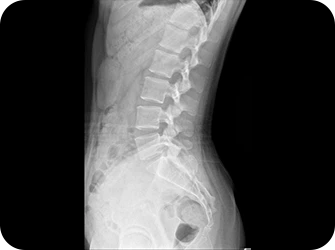

골반

허리는 골반위에 수직으로 서 있는 구조물이기 때문에 골반의 틀어짐은 필연적으로 허리를 틀어지게 만들어 허리에 많은 스트레스를 유발합니다. 만약 골반이 뒤로 기울어진 골반후방경사가 있다면 디스크탈출증을 더욱 악화시키며, 한쪽으로 회전되고 기울어진 골반은 체중이 집중되어 허리디스크와 협착증을 악화시키기 때문에 골반교정은 매우 중요합니다.